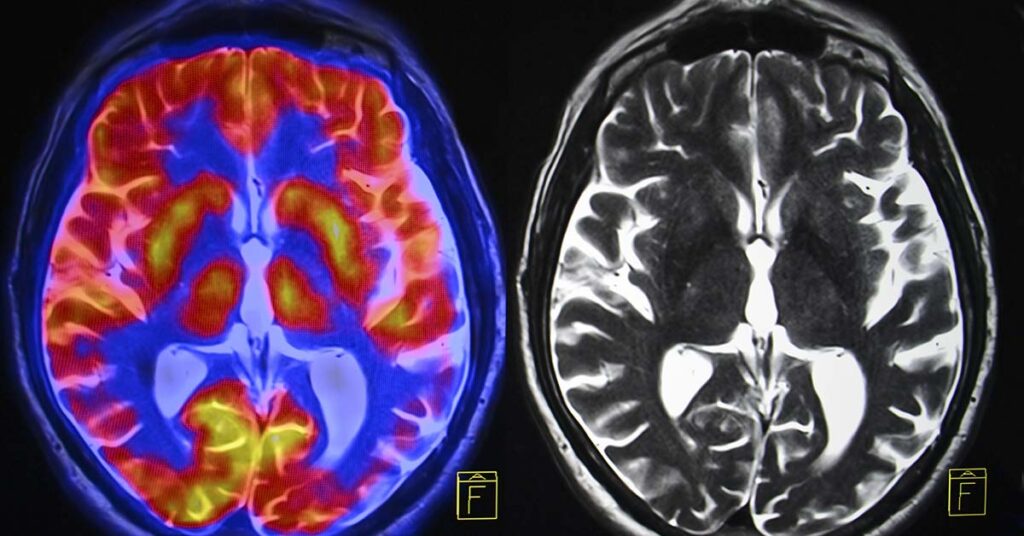

Researchers at the University of Minnesota Medical School discovered a significant warning sign that may help predict the likelihood of having an ischemic stroke or developing dementia. This research may enable doctors to treat patients earlier and improve their outcomes. The researchers sought to try and identify which sign of left atrial myopathy is the...